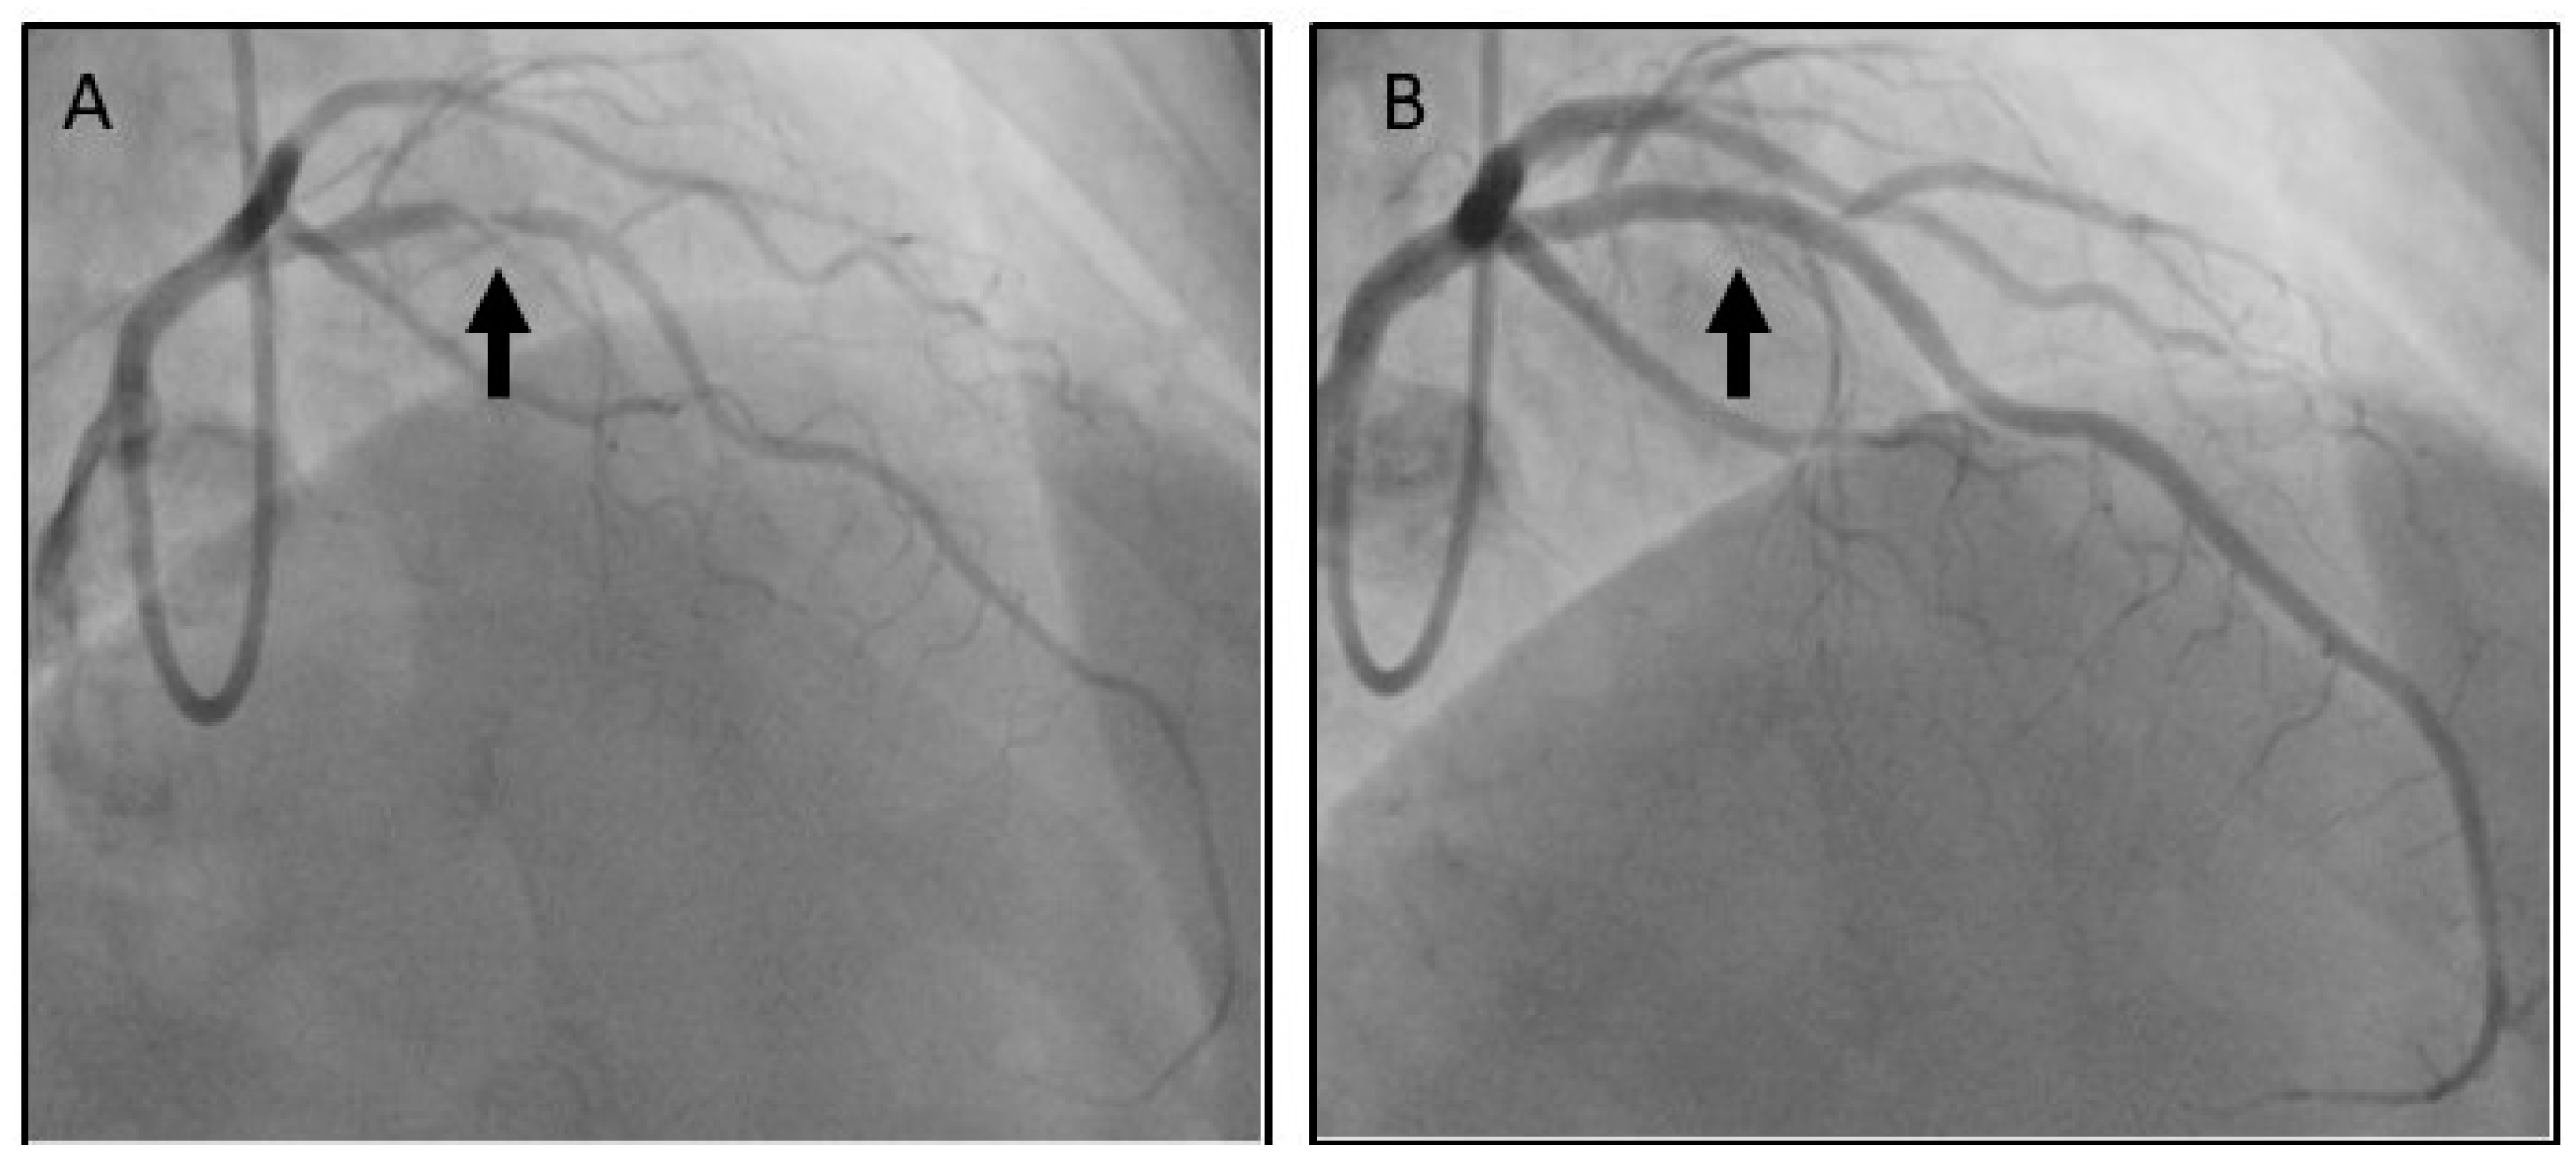

2. Case Presentation